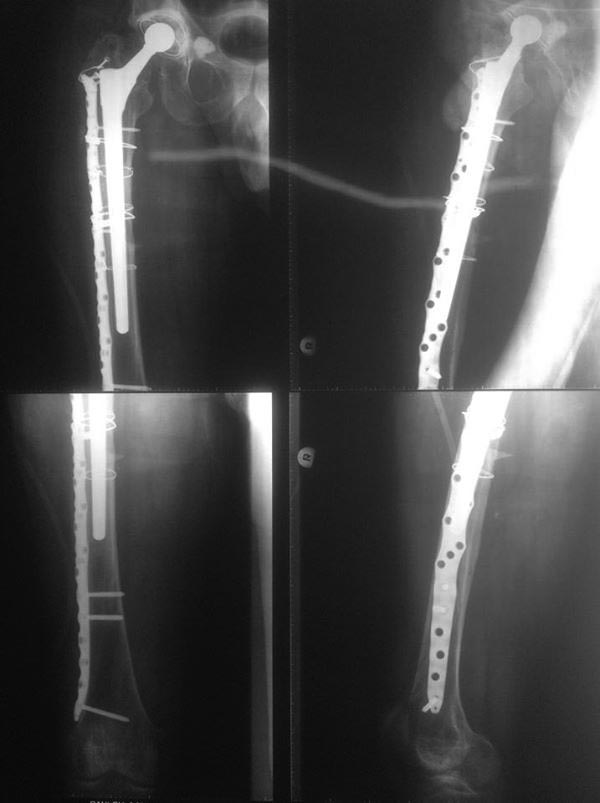

[Ortho] Перипротезный перелом

Снимки.